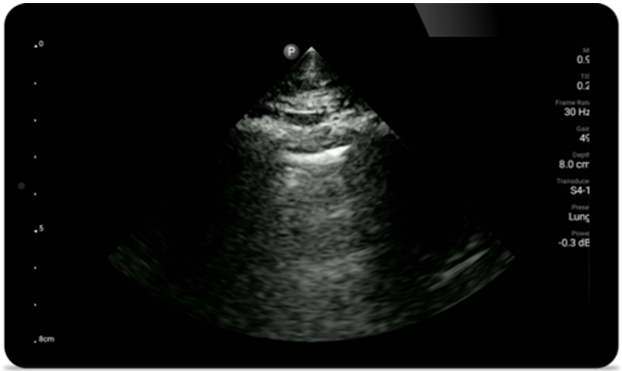

System Lumify to doskonałe rozwiązanie do badań górnych i dolnych dróg oddechowych

System Lumify do badań POCUS może służyć do wykrywania rurki dotchawiczej w tchawicy, pomagać podczas pilnych zabiegów konikotomii, diagnostyce wysięku opłucnowego oraz chorób pęcherzyków płucnych.